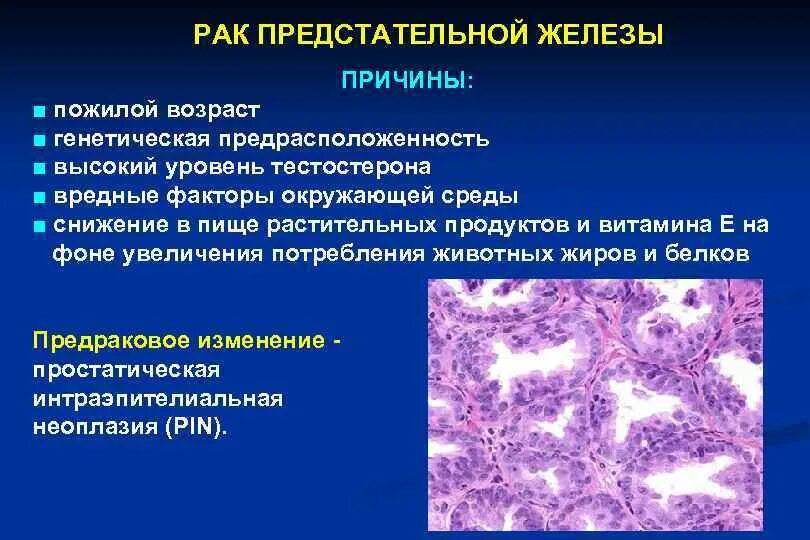

Злокачественное Перерождение предстательной железы Гистологическая классификация опухолей предстательной железы. Простатическая интраэпителиальная неоплазия. Опухоли предстательной железы факторы. Предраковые заболевания предстательной железы

Гистологическая классификация опухолей предстательной железы. Простатическая интраэпителиальная неоплазия. Опухоли предстательной железы факторы. Предраковые заболевания предстательной железы Злокачественное новообразование предстательной железы. Метастазы предстательной железы. Карцинома предстательной железы. Злокачественные новообразования простаты